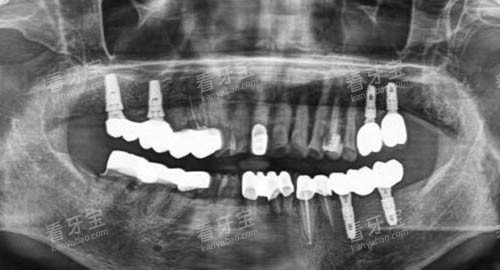

杭州美奥口腔引进了一系列国内外靠前的口腔诊疗设备,如智能化口腔全景机、口腔 CT、激光治疗设备等。

智能化口腔全景机能够快速、比较准地拍摄口腔全景图像,为医生提供超全、清晰的口腔信息,有助于比较准诊断口腔疾病。

口腔 CT 则可以提供三维立体的口腔图像,让医生更加直观地了解患者的口腔结构,为种植牙、正畸等复杂治疗项目提供正确的术前规划。